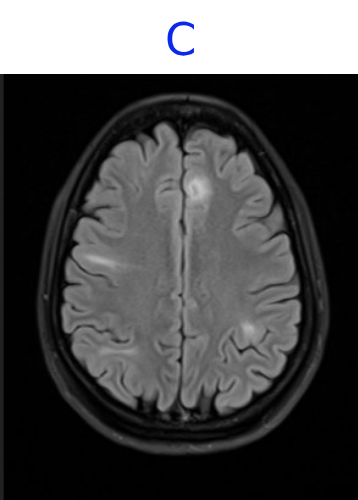

• C. MR BRAIN

• C. Areas of mild cortical thickening and blurring of the gray–white junction, consistent with focal cortical dysplasia